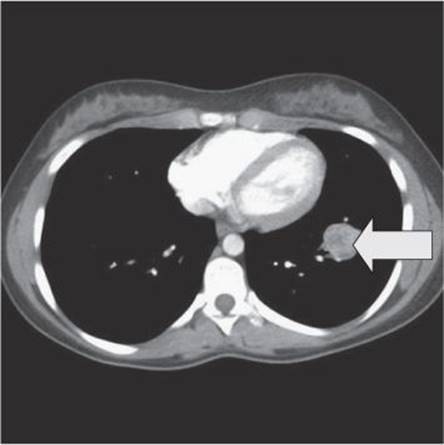

A CT scan of the chest should be done to rule out multiple metastases and define in more detail the lesion seen on the chest X-ray. A bone scan should also be done to rule out bone metastases. The CT scan showed a single lesion in the left lower lobe (Fig. 24.3).

Fig. 24.3